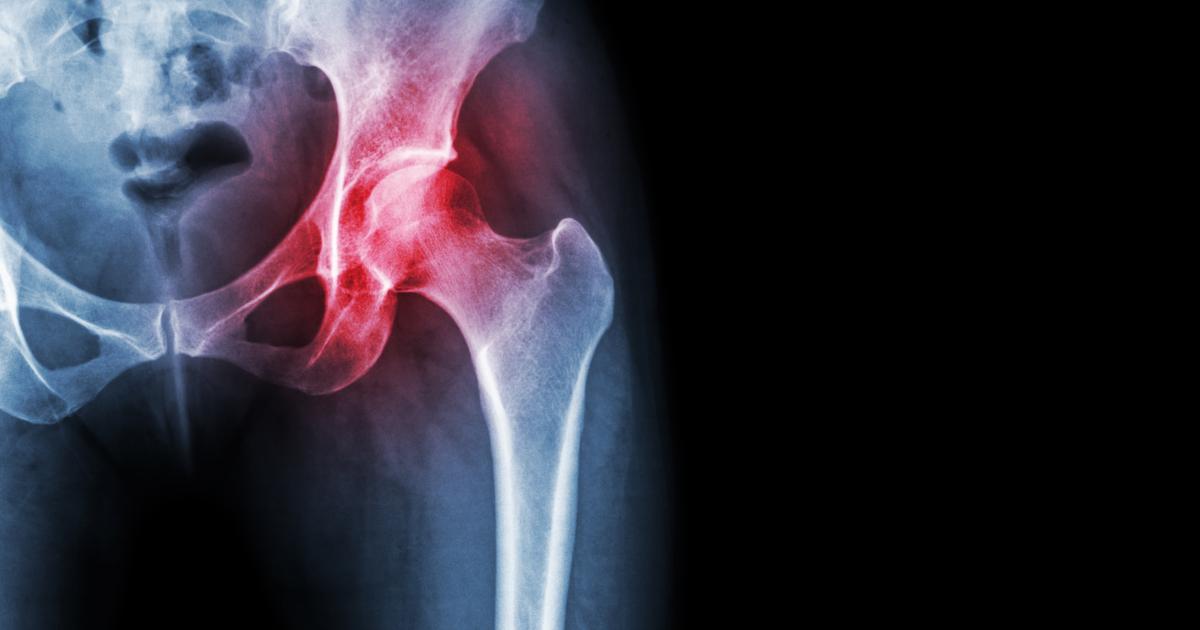

Rheumatology involves the assessment and multi-disciplinary management of joint disorders (from inflammatory and degenerative arthritis, spondyloarthritis and crystal arthritides), vasculitis, osteoporosis, connective tissue disorders and management of their related co-morbidity.